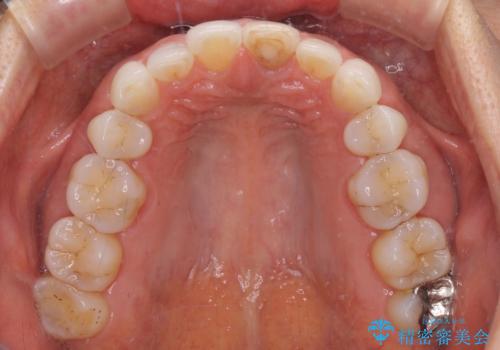

矯正治療の後戻り インビザライン・ライトでの再矯正

- 上下前歯を中心に、以前行った矯正治療の後戻りが気になるとのことで来院された患者様です。

後戻りは軽度であったため、インビザライン・ライトにて治療を行うこととしました。

矯正治療後は、再度後戻りすることを極力回避するために、下顎前歯の舌側を細いワイヤーを用いて保定することとしました。